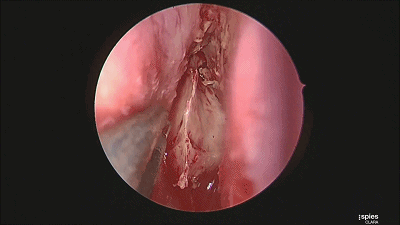

▼刮匙轻轻刮取肿瘤。

▼留取肿瘤标本。

▼本例垂体腺瘤质软,易于吸除。

▼继续仔细吸除瘤腔死角的肿瘤。